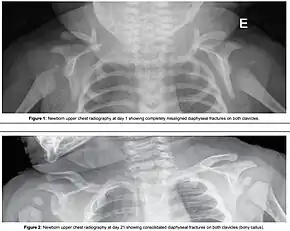

Fracture of both clavicles as a result of shoulder dystocia (top) – Post healing (bottom)

ComplicationsBaby: Brachial plexus injury, clavicle fracture[2]

Shoulder dystocia is when, after vaginal delivery of the head, the baby's anterior shoulder gets caught above the mother's pubic bone.[3][1] Signs include retraction of the baby's head back into the vagina, known as "turtle sign".[1] Complications for the baby may include brachial plexus injury, or clavicle fracture.[2][1] Complications for the mother may include vaginal or perineal tears, postpartum bleeding, or uterine rupture.[3][1]

Typically the procedures are performed in the order listed and the sequence ends whenever a technique is successful.[11] Intentional fracturing of the clavicle, a procedure known as cleidotomy,[12][13] is another possibility at non-operative vaginal delivery prior to Zavanelli's maneuver or symphysiotomy, both of which are considered extraordinary treatment measures. Pushing on the fundus is not recommended.[1]